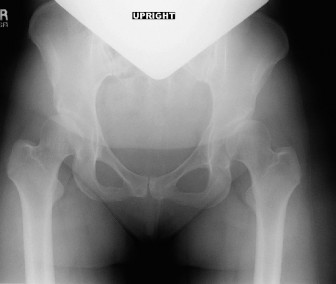

A 68-year-old, active male presents to the emergency department after being struck by a motor vehicle while r…